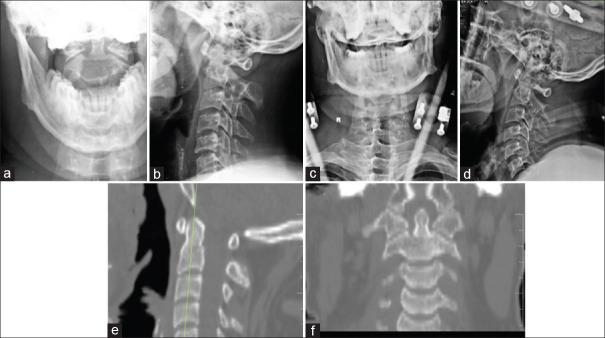

The options for the management of type II odontoid fractures in young patients include anterior screw fixation, posterior spinal fusion, or halo-vest immobilization (HVI). However, there is a recent trend away from nonoperative management and an increase in primary operative stabilization across several centers. Hence, our study aims to compare the functional and radiological outcomes of type II odontoid fractures in young patients managed with HVI and surgery.

A retrospective analysis of 70 patients with type II odontoid fracture who were managed in our institution with a mean age of 47 years was included in our study. The clinical details included the Neck Disability Index (NDI), Visual Analog Scale (VAS) for neck pain, and S-Range of Movement (ROM)-Neck score. Radiological details included union status, atlanto-dens interval, amount of displacement and angulation, and transverse ligament injury. Both the clinical and radiological parameters were compared between the patients who underwent HVI ( = 28) and surgery ( = 42).

The mean ± standard deviation follow-up duration was 4.2 ± 2.5 years in the HVI group and 3.8 ± 2.7 years in the surgery group. Of the clinical parameters, the S-ROM-Neck score was significantly better in the HVI group than in the surgery group ( < 0.001). The length of hospitalization was much shorter in the HVI group ( < 0.001). There were no differences in NDI, VAS for neck pain, and other radiological parameters.

For type II odontoid fractures in young patients, HVI had better clinical outcomes compared to the surgery and should be considered the first line of management.